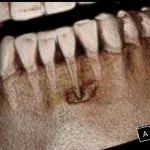

Cone Beam Case Study:  Abscess on #24